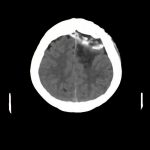

'14年5月

70代

脳腫瘍

手術前1

No.’14_86 手術前1